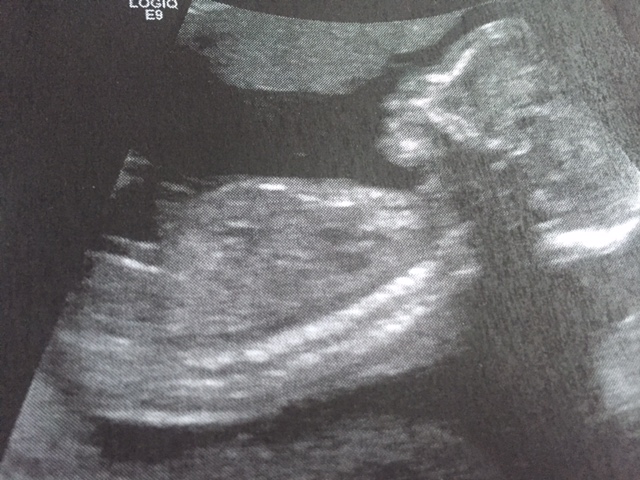

This was my 18 week scan, can anybody see my baby's gender on this? please

Possibly seeing three lines there but that's just a guess....

I'm seeing three lines here too, but I think I also see something long like boy parts.

Very very tricky but I think boy.

I think girl

I think girl.

I think there might be boy parts hiding in the shadow

The three lines look quite far apart - I see that shadow too & would guess boy.

Gender wasn't in focus because this was just a measurement of the leg but it could go either way. Leaning more boy than girl but hard to tell xx

I'd guess boy it does look like a scrotum with a shadow x

Looks to me boy going by that shadow. It is a very much boy shaped shadow.

70% guess on girl xx

Girl

Any more guesses?